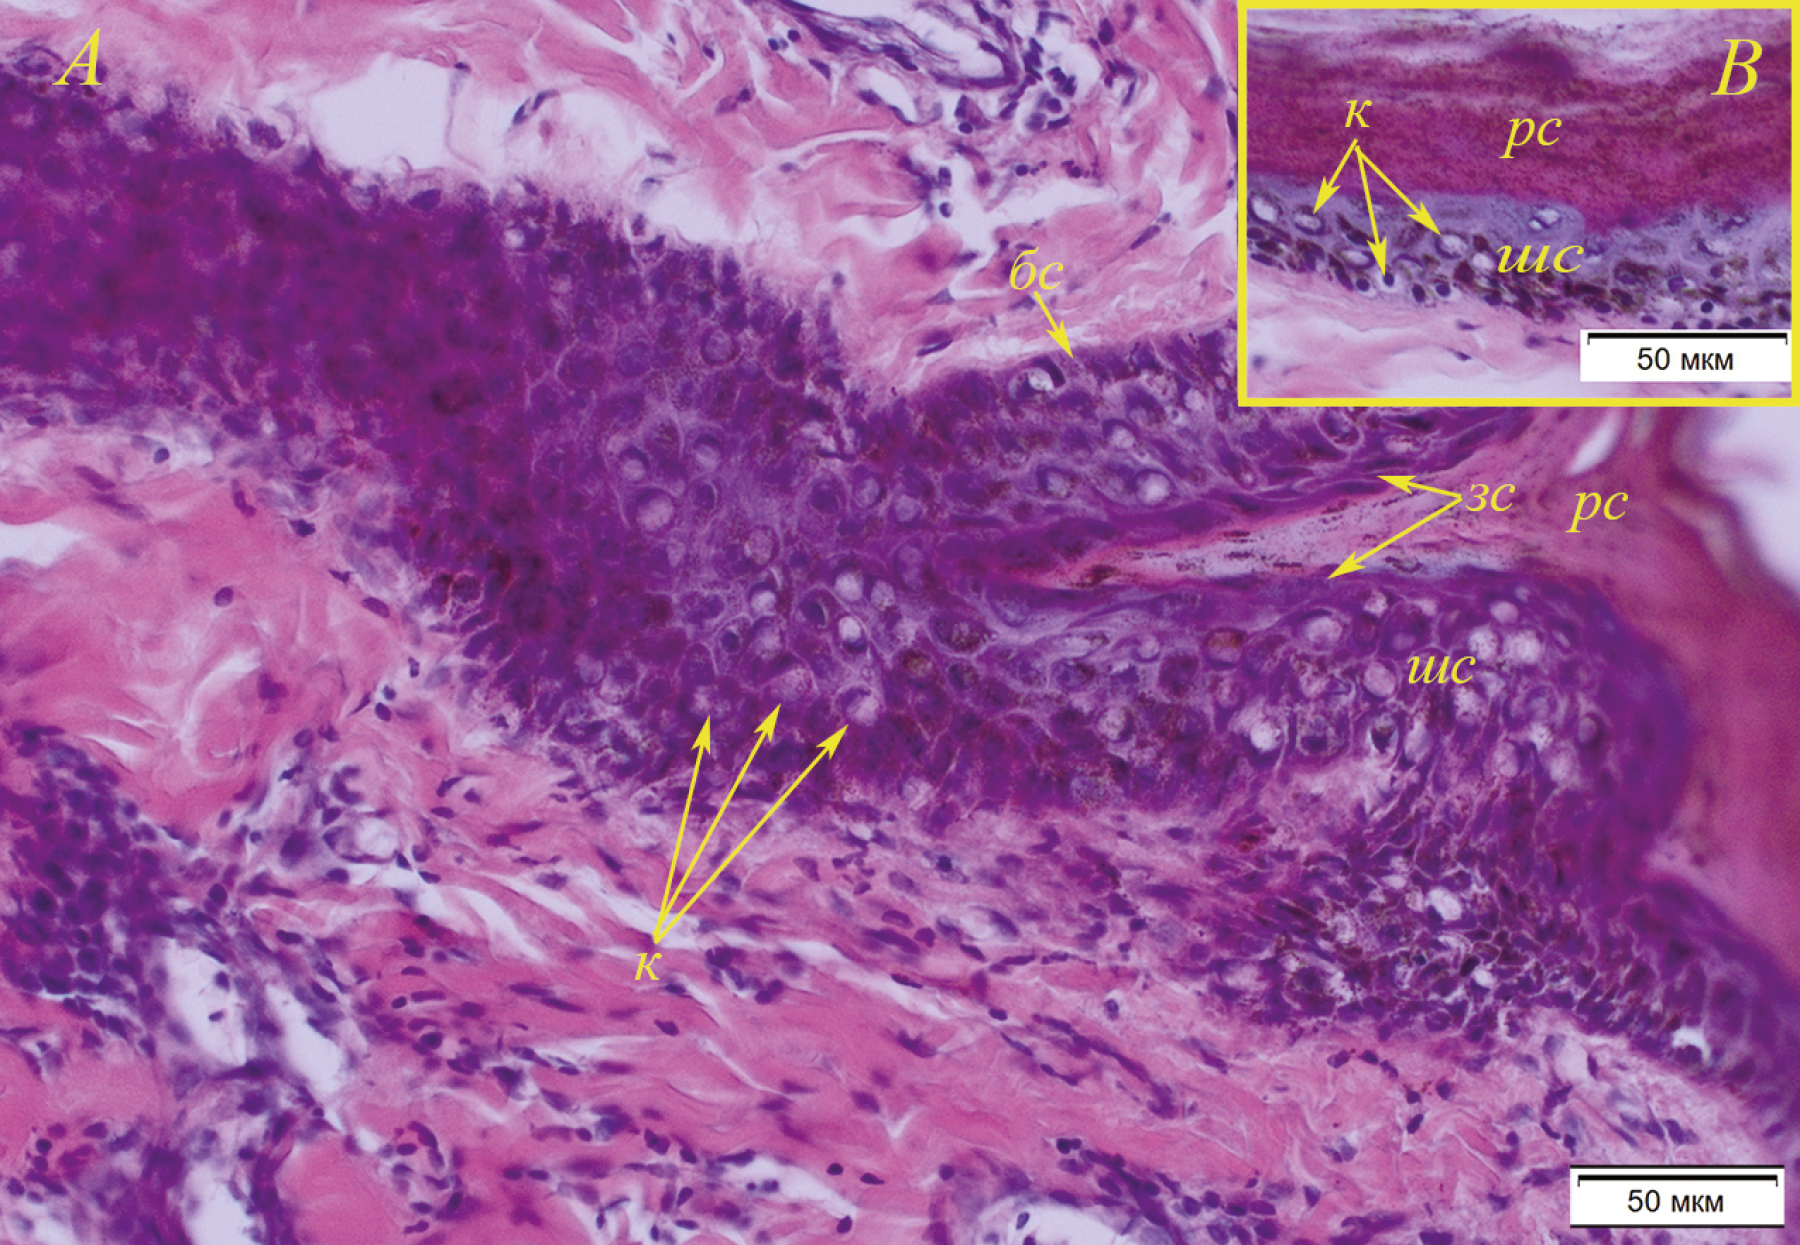

С помощью анатомических и гистологических методов мы изучили норму и патологические изменения кожного покрова у 12 разновозрастных особей байкальской нерпы (Pusa sibirica) (алопеция, язвы, шрамы и др.). Такие изменения обычно присутствуют у многих особей, выходящих на береговые лежбища. Норма: кожа имеет складчатый эпидермис на теле и ластах. Отмечен гиперкератоз эпителия. Граница между сосочковым и сетчатым слоями дермы не выражена. Сосочковый слой образован тонкими пучками коллагеновых волокон, сетчатый слой сформирован толстыми пучками коллагеновых волокон. В сетчатом слое кожи туловища присутствуют мощные, многочисленные пучки гладких мышц. Дерма кожи ласт тоньше в сравнении с дермой кожи туловища нерп. В коже тела сальные железы небольшие многодольчатые, каждый волосяной пучок окружают, как правило, две такие железы. Нижние секреторные отделы апокриновых потовых желез слабо извитые трубчатые, располагаются в глубоких слоях сетчатой дермы и в жировой клетчатке отдельно от волосяных фолликулов и рядом с сетью кровеносных сосудов. Их узкие выводные протоки открываются в воронку волоса на уровне его верхней трети. В коже ласт крупные извитые апокриновые железы залегают на уровне нижних отделов луковиц остевых волос, удлиненные полиморфные выводные протоки сальных желез открываются в волосяные сумки. Обсуждаются морфофизиологические адаптации кожного покрова нерп, способствующие улучшению его гидродинамических, терморегуляторных и солнцезащитных свойств. Патология: выявлены два основных комплекса патологий кожи нерпы: 1) койлоцитоз, субэпидермальное воспаление (инфильтрат представлен лимфоцитами с небольшой примесью гистиоцитов), экзоцитоз лимфоцитов в волосяные фолликулы с явлениями спонгиоза; 2) формирование субэпидермального пузыря с нейтрофильной инфильтрацией в сосочковом слое дермы. Эти патологии могут быть связаны с потеплением климата и изменением ледового режима Байкала, что привело к возникновению иммунных воспалительных процессов в коже. Не исключено и воздействие неизвестного вирусного патогена, вызвавшего койлоцитоз у нерп.